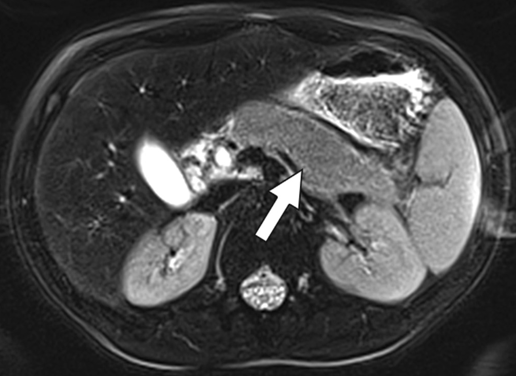

Following the thorough analyses of pediatric renal and liver tumors by Ayyala and Squires, respectively, Trout shared his multimodality assessment of adrenal tumors—staging, treatment response, the role of nuclear medicine—with Dillman joining to discuss peritoneal, mesenteric, and omental disorders, as well as congestive hepatopathy and Fontan-associated liver disease. (Fig. 3). For more Trout and Dillman research, turn to page 16 for a summary of their study on reduced-dose CT for lung nodules in children and young adults with cancer.